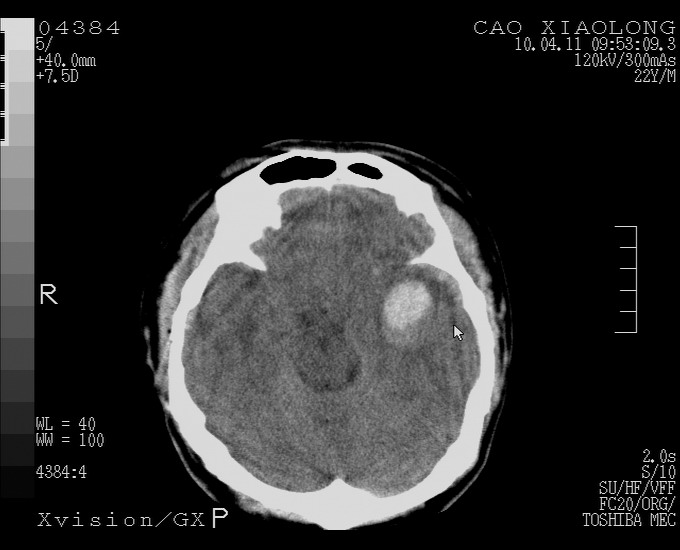

以下是引用随光逐影在2010-4-11 11:00:00的发言:[br]1)左侧额颞顶部硬膜下血肿。2)蛛网膜下腔出血。3)右侧颞顶部颅骨线形骨折。[br][br]20小时后复查:左侧额颞叶脑挫裂伤;左侧额颞顶部硬膜下血肿及蛛网膜下腔出血有吸收表现;右侧颞顶部颅骨线形骨折。[br]